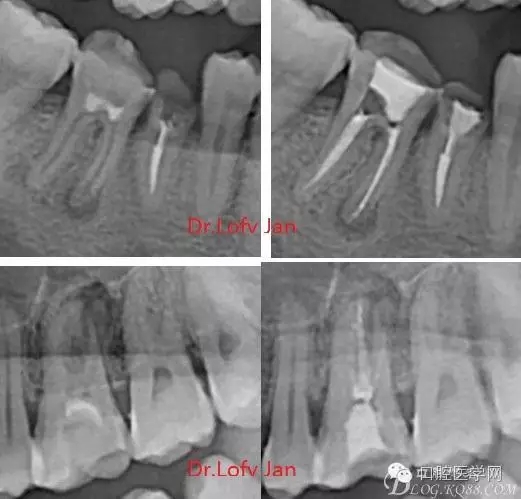

前言:自己做的一些曲面斷層片在未試尖根管治療中的病例整理,發(fā)現(xiàn)問題很多包括自身的,技術(shù)的,還有設(shè)備的問題,予以總結(jié)整理并期待進(jìn)一步提高。

根管治療術(shù)是牙體牙髓疾病治療中最復(fù)雜和最關(guān)鍵的治療項(xiàng)目。根管充填材料抵達(dá)根尖、并能嚴(yán)密堵塞根尖孔,是確保根管治療效果的關(guān)鍵指標(biāo)。為了保證根管充填到位,醫(yī)生需要在術(shù)前照牙片以了解牙根根管的數(shù)量、彎曲程度和長度,在術(shù)中有時(shí)需要插針照牙片來精確測量根管長度,術(shù)后必須照牙片以確定是否根管充填到位,如果欠填或超填,就需要重新充填、重新照牙片確認(rèn),直到根管充填到位。所以,在患者接受根管治療時(shí)有時(shí)會反復(fù)照牙片。

《數(shù)字化根尖片、曲面斷層片、CBCT測量牙齒長度準(zhǔn)確性的比較研究》文中顯示:平行投照數(shù)字化根尖片影像長度和牙齒實(shí)際長度之間無顯著性差異(P0.05);數(shù)字化曲面斷層片影像長度和牙齒實(shí)際長度之間有顯著性差異(P0.05),平均失真率為17.05%。CBCT冠狀面測量結(jié)果中除上頜前磨牙區(qū)、下頜前磨牙區(qū)與真實(shí)長度差異無統(tǒng)計(jì)學(xué)意義(P0.05)外,其余6個(gè)分區(qū)差異均有統(tǒng)計(jì)學(xué)意義(P0.05);矢狀面測量結(jié)果中上頜磨牙區(qū)、下頜磨牙區(qū)、下頜前磨牙區(qū)、下頜尖牙區(qū)、下頜前牙區(qū)與真實(shí)長度比較差異均有統(tǒng)計(jì)學(xué)意義(P0.05)。結(jié)論平行投照數(shù)字化根尖片較曲面斷層片和CBCT能更加精確地反映牙齒的真實(shí)長度。

病例分析:曲面斷層片在x線輔助診斷與檢查中目前大多數(shù)文獻(xiàn)和著作都建議只能作為初診拍片檢查手段,不能作為終末疾病的確診與手術(shù)療效的評價(jià)指標(biāo),臨床大部分中小型門診都因?yàn)樵O(shè)備不齊全導(dǎo)致信息偏差很大。